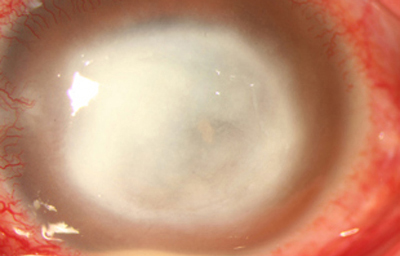

Superficie corneal irregular y grisácea, (Fig. 1, 2) con opácidades granulares en parche y formación de líneas epiteliales elevadas de aspecto granular (Fig. 3), que pueden arborizar dando imágenes de pseudodendritas. Opacidades superficiales satélites. (Figura 4) Inyección ciliar. Ulceración epitelial variante. (Figura 5).

Fig. 2 Síntomas de 25 días evolución